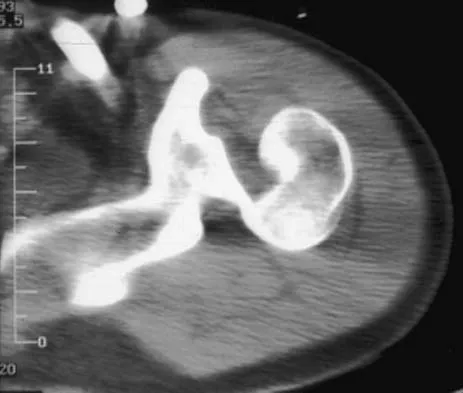

A 21-year-old patient has had pain and a marked decrease in active and passive shoulder motion after having had a seizure 2 months ago as the result of alcohol abuse. Current AP and axillary radiographs and a CT scan are shown in Figures 26a through 26c. Management should consist of

Open reduction and subscapularis and lesser tuberosity transfer into the defect is the treatment of choice in young individuals who have defects that involve between 20% to 45% of the head. Disimpaction and bone grafting is an option in injuries that are less than 3 weeks old. Closed reduction 2 to 3 months after injury usually is unsuccessful and increases the risk of fracture or neurovascular injury. Total shoulder arthroplasty is reserved for defects of greater than 50% or with associated glenoid surface damage. Hemiarthroplasty should be avoided in young individuals unless 50% or more of the head is involved. Gerber C: Chronic locked anterior and posterior dislocations, in Warner JJ, Iannotti JP, Gerber C (eds): Complex and Revision Problems in Shoulder Surgery. Philadelphia, PA, Lippincott-Raven, 1997, pp 99-113.